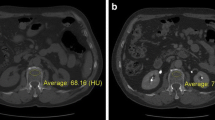

On sagittal reformations, circular VOIs were manually placed in the ventral halves of L1 to L3. If one or more of these showed a pathology such as a fracture or extensive degenerative changes, adjacent thoracolumbar vertebrae were used instead. CT numbers in NE, arterial (AR), and portal-venous (PV) phases were extracted from both conventional and two virtual monoenergetic images at different energy levels (VMI; 50 and 200 keV), respectively (Fig. 1).

Additionally, mid-luminal iodine concentrations (mg/ml) were measured within the abdominal aorta (AA) and the inferior vena cava (IVC) on axial images—immediately inferior to the renal vessels—as well as within the vena portae (VP) on multiplanar reformations (Fig. 1). A commercially available spectral CT software was used for the generation of iodine density maps based on iodine-water decomposition (IntelliSpace Portal 10.1.0, Philips Healthcare).

For DLCT-BMD, measurements in native scans averaged to 102.95 ± 46.33 mg/ml (mean ± SD), whereas arterial (112.23 ± 7.88 mg/ml [+ 9.0%]) and portal-venous (126.86 ± 53.89 mg/ml [+ 23.2%]) scan phases revealed substantially higher results (Fig. 2). DLCT-BMD from AR and PV showed high correlations (r = 0.994 [95% confidence interval, 0.991–0.996] and r = 0.989 [0.984–0.992]), yet a low agreement with DLCT-BMD from NE.

Conventionally calculated BMD showed similar, yet continuously lower results: native BMD values were 97.00 ± 43.48 mg/ml, whereas in CE phases, likewise, BMD values were substantially higher with 106.44 ± 44.35 mg/ml (+ 9.7%) for AR and 119.67 ± 42.93 mg/ml (+ 23.3%) for PV, respectively.